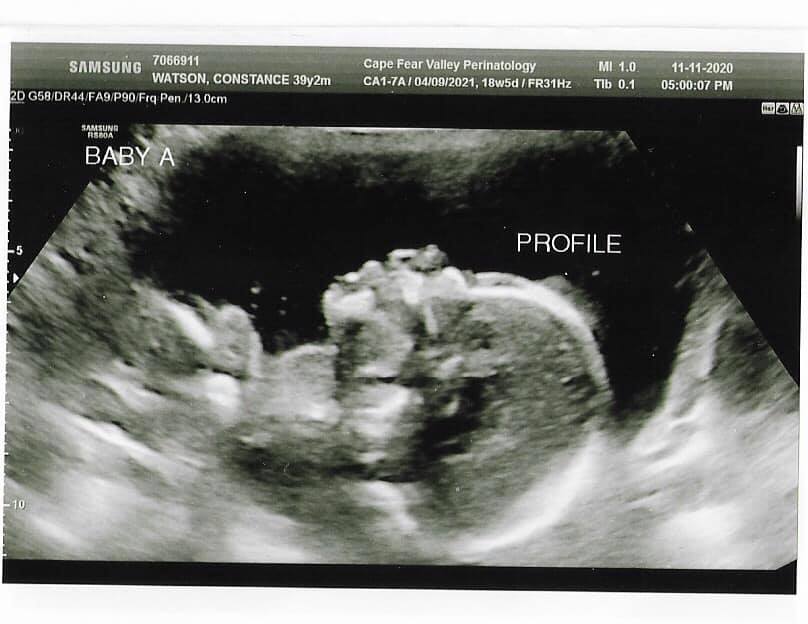

When I was 16 weeks pregnant with the twins, we learned that they were both girls and we gave them their names. Twin A was named Jordan Suzanne, and Twin B was named Ariana Catherine.

At the same time, however, we were also informed that Twin B, Ariana, had anencephaly, a birth defect where the skull and scalp don't fully close, leaving the brain open.